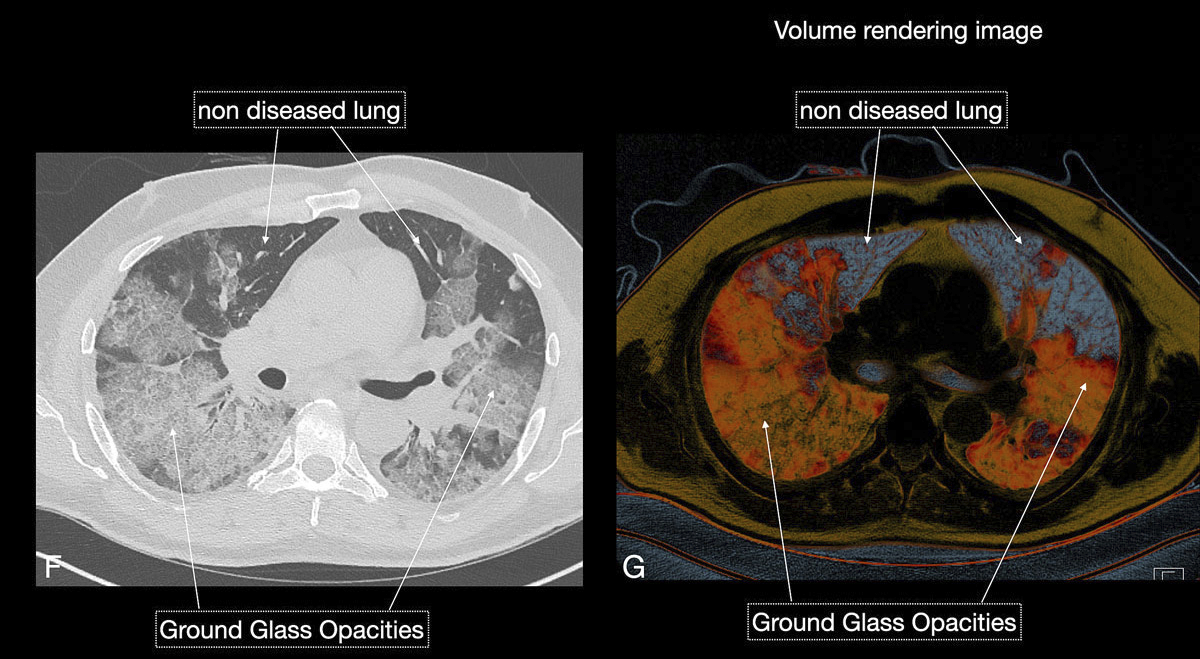

Figure 3 EF Over time the clinical condition worsened, chest x-ray (E) demonstrated persisting, but mildly improving peripheral consolidations, and chest CT (F) demonstrated features of reparative organising pneumonia. The patient’s condition deteriorated and he died from septic and cardiogenic shock 12 days after intubation.

Figure 6 FG Chest CT (F) and corresponding volume rendering (G) image demonstrated the increasing extent of diseased (orange) versus non-diseased (grey-blue) lung parenchyma.

Figure 6 GH Three-dimensional volume rendering images (H) gave an overview of diseased total lung. The patient required no respiratory assistance.